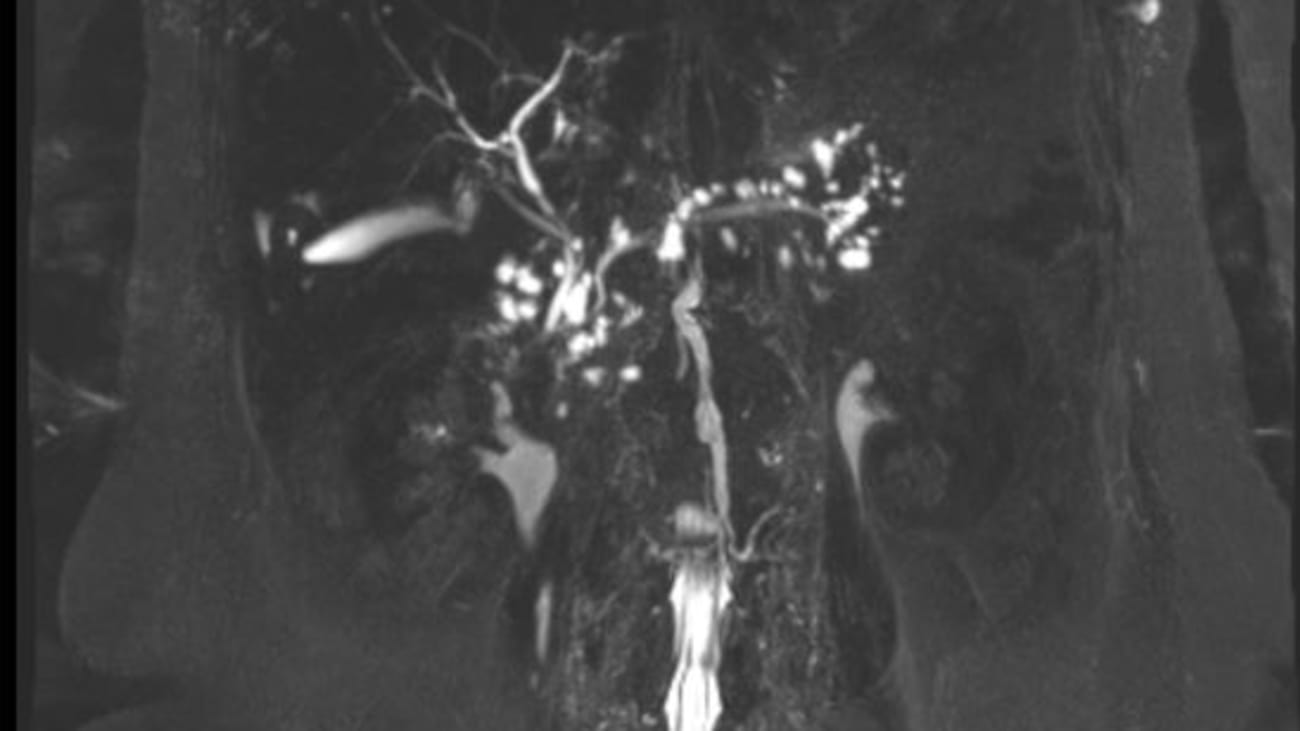

Specialized treatment, including total pancreatectomy and islet cell autotransplantation, for patients with serious or chronic conditions is also. Pancreatic cancer early detection team at johns hopkins brings together experts in gastroenterology, pathology, radiology, surgery and genetics using advances in genetic research and diagnostic technologies to create a multidisciplinary early detection research program. As many as ten different tumor types have been lumped under the umbrella term cancer of the pancreas, classified as exocrine or endocrine tumors.each of these tumors has a different appearance when examined with a microscope, some require different treatments, and each carries its own unique prognosis.

1 department of oncology, sidney kimmel comprehensive cancer center, johns hopkins university, baltimore, maryland. Bert vogelstein and his team at johns hopkins kimmel cancer center, can detect the early presence of multiple cancers, including pancreatic cancer, and also can identify where in the body the cancer began. Due to its proximity to the pancreas, the duodenum is the section of the small intestine most often affected by pancreatic cancer.

Pancreas cancer is a complex disease requiring the integration and expertise of specialists from many medical and surgical disciplines. Researchers have found that pancreatic cysts can be precursors to pancreatic cancer. This cancer occurs in the lining of the ducts in the pancreas.